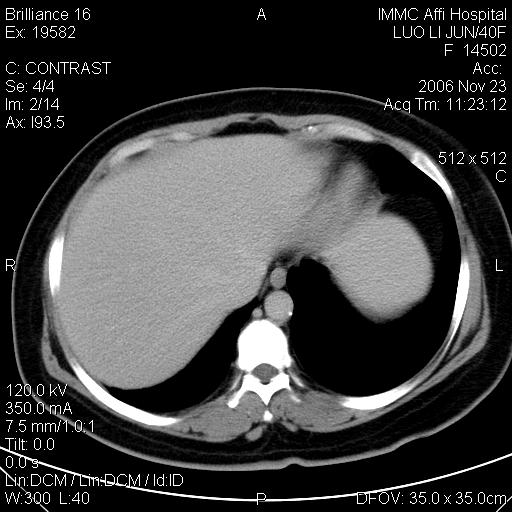

标题: CT5664:我也发一个肝脏的片子大家看看

很典型的肝癌。

速升速降,典型肝癌.

是啊,典型的早出早归!

快进快出典型肝癌.

符合肝癌的增强特征。支持肝癌!

很好的片子,可惜增强做的比较失败,a期时间没有把我好,实际到了静脉早期了,否则会更典型。

最终考虑是肝腺瘤